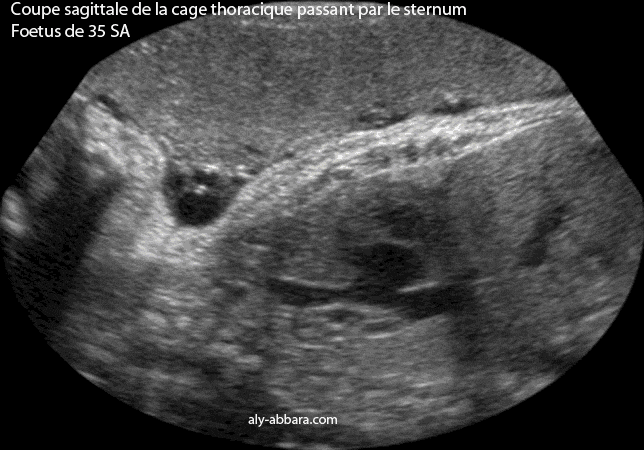

Coupe sagittale, antéro-postérieure, de la cage thoracique montrant l'aspect échographique du sternum.

Il s'agit d'un fœtus âgé de 35 SA